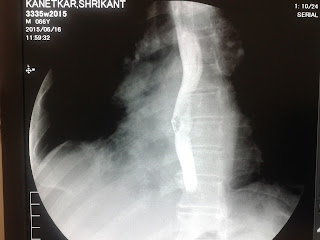

An elderly person accidentally ate a tablet along with its foil followed by severe chest pain.

Gastrograffin swallow study was done-

There was a esopahegal tear with leak into the right pleural space. It was managed conservatively. After 1 month he developed right sided empyema. So the tear was sealed by a plugging device. Gastrograffin swallow done after the procedure did not reveal any leak.